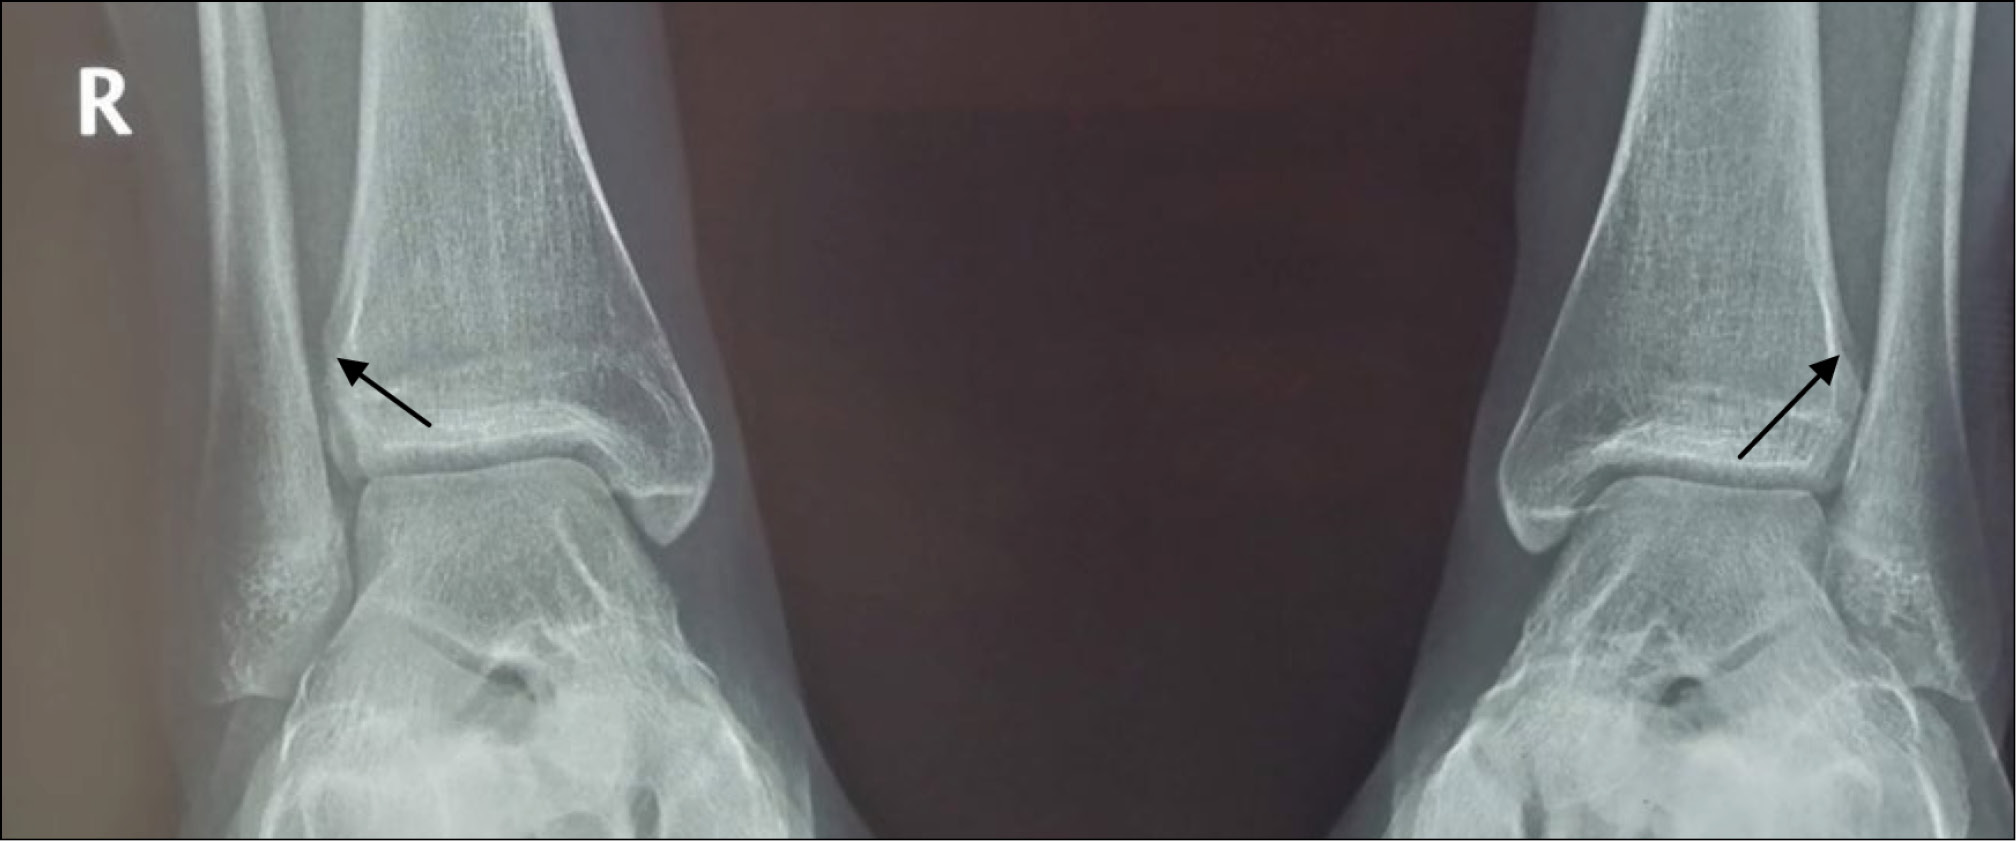

Пациентка А.А., 13 лет, диагноз: «Закрытый эпифизарный перелом переднего бугорка правой большеберцовой кости со смещением. Разрыв дистального межберцового синдесмоза». Ребёнок поступил в отделение спустя 3 нед с момента травмы с жалобами на боль при ходьбе и чувство нестабильности в правом голеностопном суставе. Травма получена в результате непрямого супинационно-инверсионного механизма. Первоначально пациентке поставлен диагноз: «Дисторсия связочного аппарата правого голеностопного сустава», рекомендована иммобилизация на 2 нед полужёстким ортезом. Клинически наблюдали пастозность в области правого голеностопного сустава, локальную болезненность при пальпации. Для определения повреждения межберцового синдесмоза использовали клинические тесты: тест сжатия и тест внутренней ротации стопы. Оба теста оказались положительными. Пациентке было выполнено рентгенологическое исследование в прямой и боковой проекции (рис. 1). Для уточнения наличия повреждения межберцового синдесмоза дополнительно сделаны рентгенологические снимки в синдесмозной проекции в сравнении со здоровым суставом под нагрузкой (рис. 2). В связи с тем, что клинически и рентгенологически обнаружили признаки повреждения межберцового синдесмоза, для уточнения характера повреждения использовали метод УЗ-диагностики. Обнаружены свободный костный фрагмент в проекции межберцового промежутка и наличие анэхогенных включений в области вплетения связки, что служит достоверным признаком разрыва. Поскольку были найдены достоверные признаки разрыва, и имелся выраженный болевой синдром, проба с наружной ротацией стопы не проводилась (рис. 3).

Рис. 1 (a, b). Рентгенограммы пациентки А.А. в прямой и боковой проекции. Перелом переднего бугорка правой большеберцовой кости со смещением.

Fig. 1 (a, b). X-rаy of the patient AA in frontal and lateral side. Epiphyseal fracture of the anterior tubercle of the right tibia with displacement.

Рис. 2. Рентгенограммы пациентки А.А. в синдесмозной проекции под нагрузкой по сравнению со здоровым суставом. Увеличение межберцового расстояние справа.

Fig. 2. X-rаy of the patient AA in syndesmotic side underweight compared to a healthy joint. Increased tibiofibular distance to the right.